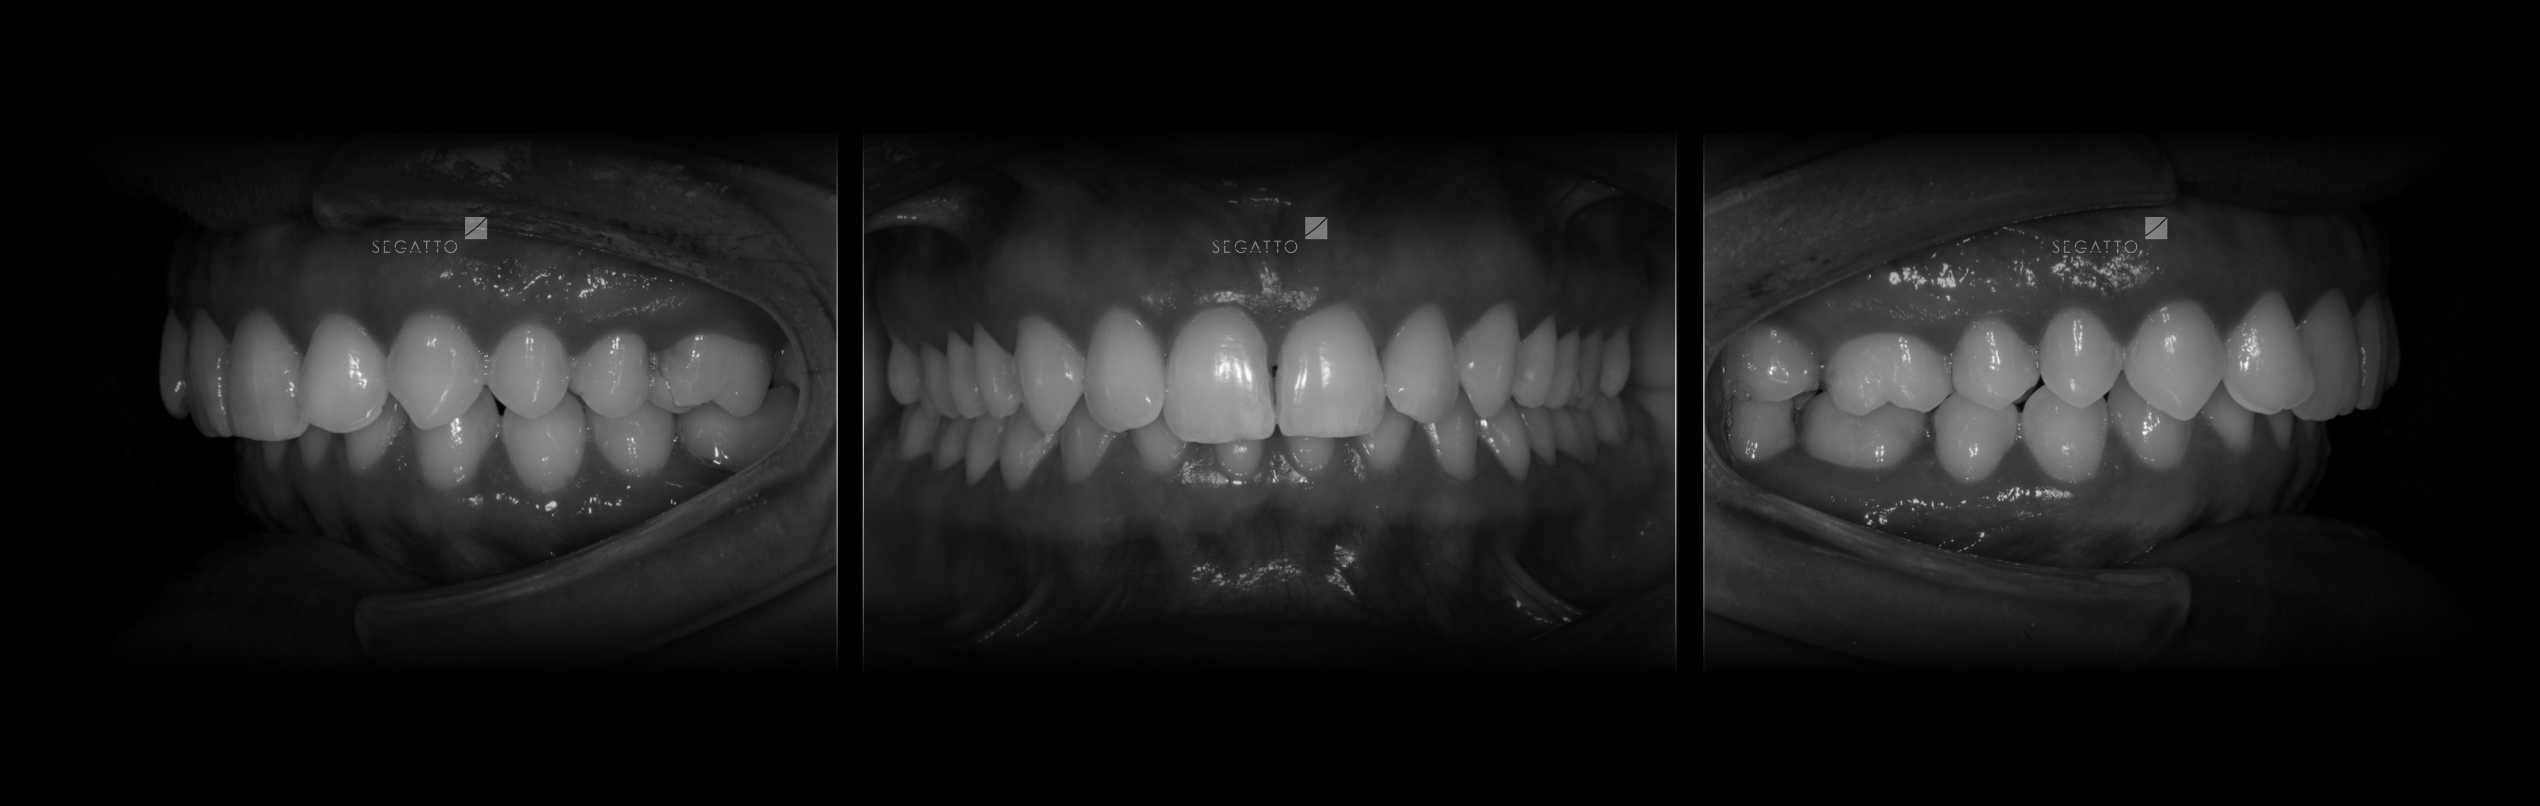

Orthodontics

Cases